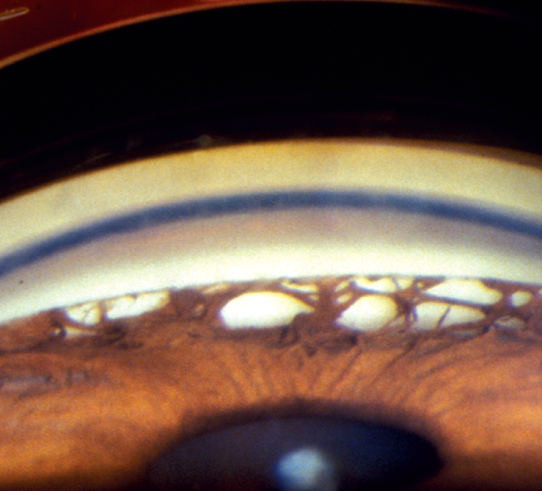

Figure 9.5.1: Chronic angle closure glaucoma with peripheral anterior synechiae.

Gonioscopy reveals broad bands of PAS in the angle in most patients. In some patients there is no PAS, despite having iridotrabecular contact on indentation gonioscopy. The PAS block visualization of the underlying angle structures. Glaucomatous optic nerve and visual field defects.